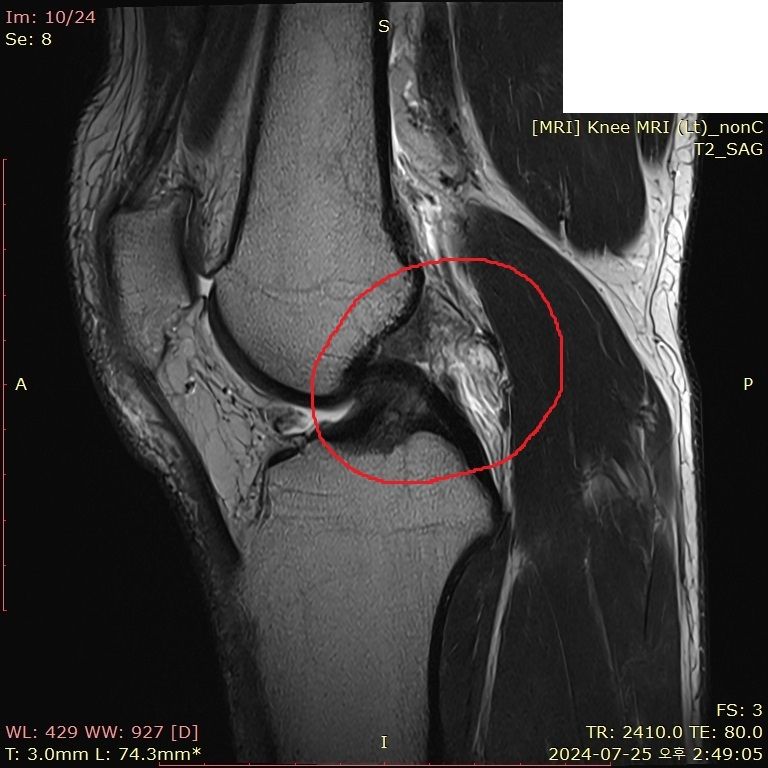

무릎 부딪혔는데 mri 한번 봐주시면 감사하겠습니다..

뛰다가 넘어졌습니다.. 예전에는 무릎이 부어도 병원 안 갔는데, 최근에는 중요성을 알아서 미리미리 검진 받자는 의미로 갔다왔습니다

• 4번 째 사진

보여주신 MRI만 보면 전방, 후방 십자인대 손상이 의심되지 않습니다.